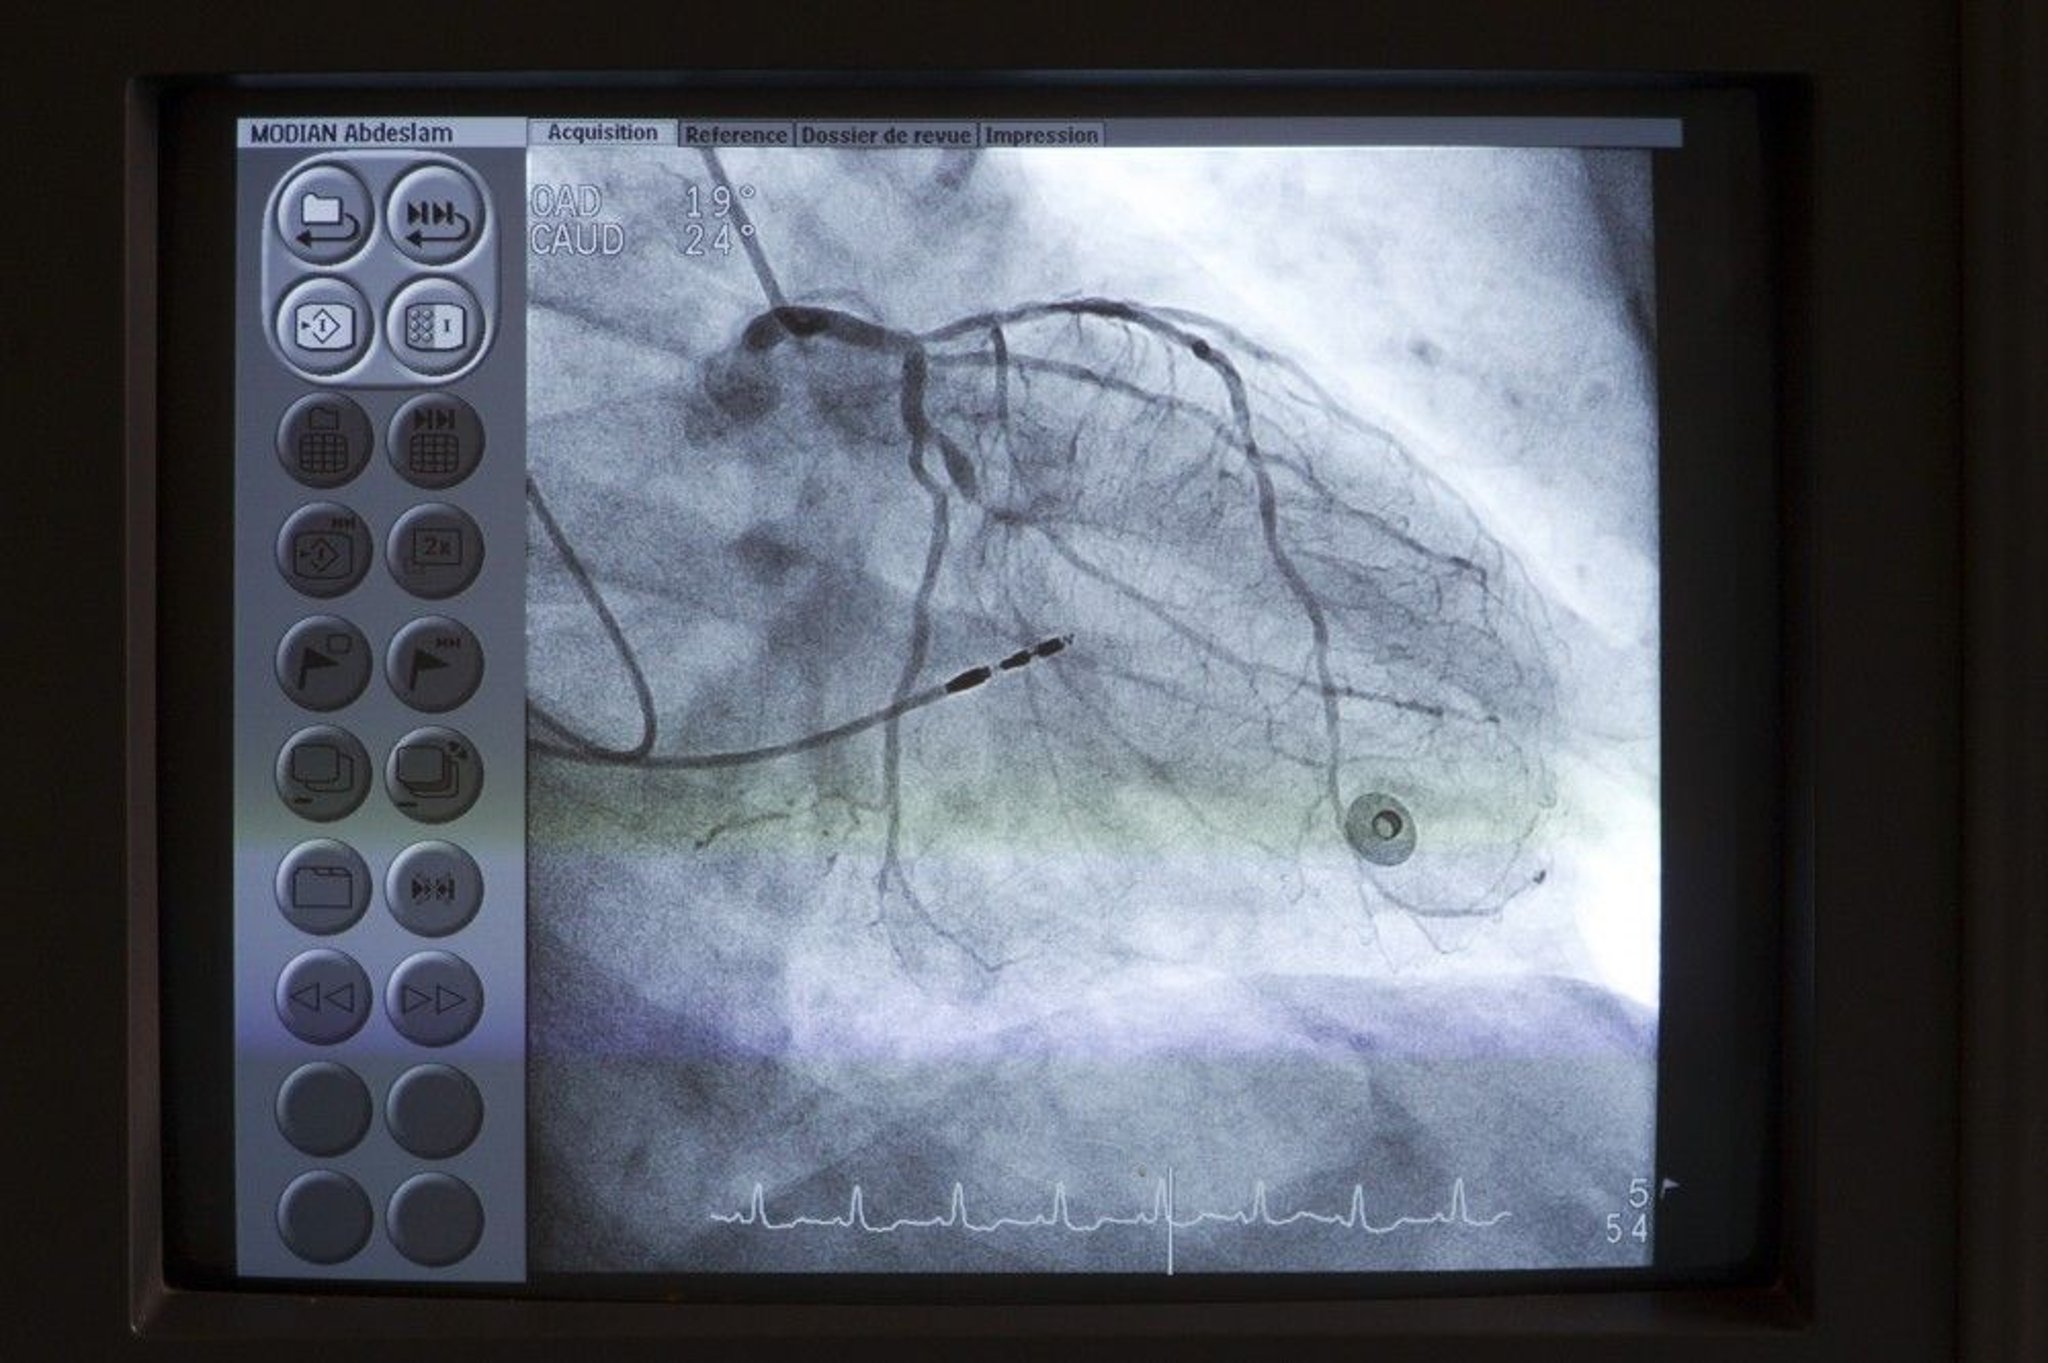

Coronary Angiography

A catheter (upper left) is placed at the os of the left main coronary artery. Contrast is then injected into the coronary arteries under fluoroscopy to detect any anomalies such as stenoses.

Astier/BSIP/SCIENCE PHOTO LIBRARY